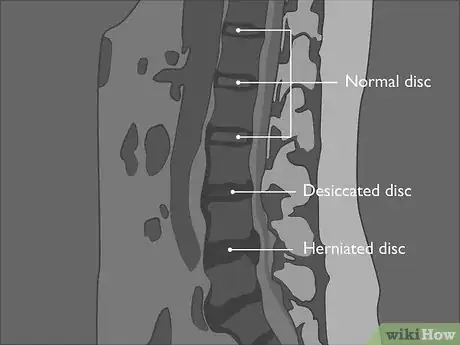

2Label the discs between the vertebrae. Each of the vertebrae of your lumbar spine is separated by a disc that acts as a cushion for the vertebrae. Your discs keep the bones of your spinal column from rubbing against each other when you move. They are labeled using the number of the vertebrae above and below them, separated by a hyphen.[7]

- For example, the disc between the third lumbar vertebra and the fourth lumbar vertebra is referred to as L3-4. Looking at your sagittal image, you should be able to determine the name for each of the discs in the lumbar region of your spine.

- The disc under L5 sits between the last vertebrae of the lumbar region and the first vertebrae of your sacrum, so it is referred to as L5-S1.

3Compare the thickness of your discs. Normally, your discs will be of more or less uniform size and similar shape. A normal disc wouldn't protrude beyond the edges of the upper or lower vertebrae. You might think of the disc as sandwiched between two vertebrae. If you had a relatively neat sandwich, the food inside wouldn't stick out from the edges of the bread. [12]

- A disc that is thinner than the others is "desiccated." Disc desiccation refers to a loss of height or thickness in the disc and is a natural product of aging (this is why people get shorter as they get older). However, if you have too much desiccation, your vertebrae may grind together when you move.

- A disc that protrudes from the sides of the vertebrae is herniated. If the herniation creates too little space for nerves in the spinal canal, this can lead to pain and discomfort.

Tip: You'll likely see more desiccation at the L4-5 and L5-S1 levels, since these are the most mobile levels of the lumbar region of the spine.